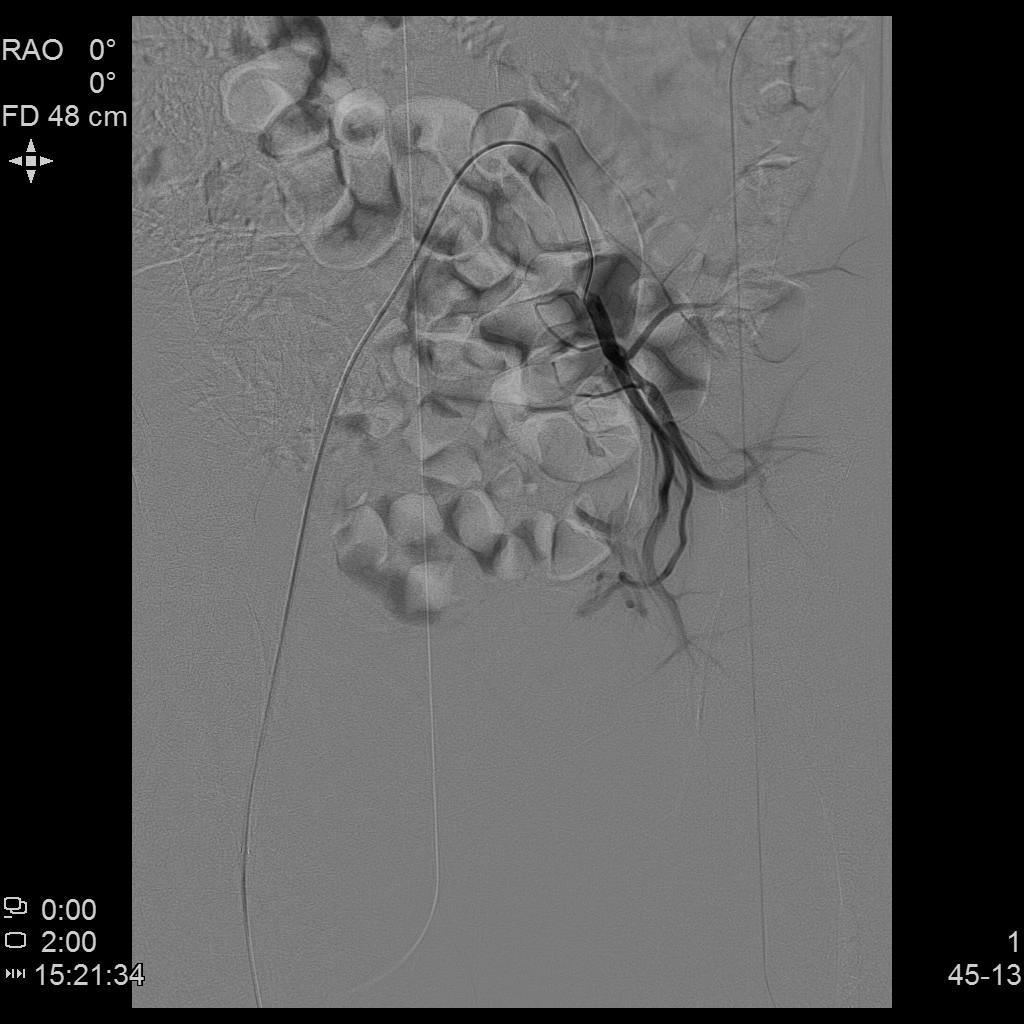

例2

中年患者,患有“子宫腺肌瘤”7年余,长期受痛经、月经量增多困扰,严重影响生活质量。经多处求医,经历药物调理、“曼月乐”宫腔植入、“海扶刀”消融术等多种治疗,痛经、月经量多等情况一直无法有效缓解,日渐严重。

- 术前MRI检查显示子宫明显增大。

术前MRI检查显示子宫明显增大

- 经UAE治疗后,术后痛经、月经量增多等症状迅速得到缓解,生活质量明显改善。术后3月上述症状基本消失。

- 插管至右侧子宫动脉,显示子宫右侧病灶情况

右侧子宫动脉造影

- 插管至左侧子宫动脉,显示子宫左侧病灶情况

左侧子宫动脉造影

- 术后4个月复查,子宫明显缩小,腺肌瘤明显坏死吸收,相关症状基本消失。

术后复查MRI显示子宫明显缩小,腺肌瘤明显坏死吸收